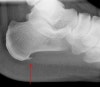

6~8주 정도의 보존적 치료로도 좋아지지 않을 때, 전신 증상, 휴식 시에도 통증이 있는 경우는 선 자세에서 lateral view X-ray 검사를 합니다.

환자의 약 50%에서 족저근막의 바로 위층에 위치한 짧은 굽힘근(flexor brevis)의 기시부에 발꿈치 골극(heel spur; enthesophyte)가 발생하나 통증의 근원은 아닙니다(족저근막염이 없는 성인의 20%가 골극이 있습니다).

골극이 물리적으로 연부조직을 자극하고 있는 것이 통증의 원인이 아니라 단지굴근건 부착부의 염증과 점액낭염이 그 원인입니다.

X-ray : 족저근막염(Plantar fasciitis)